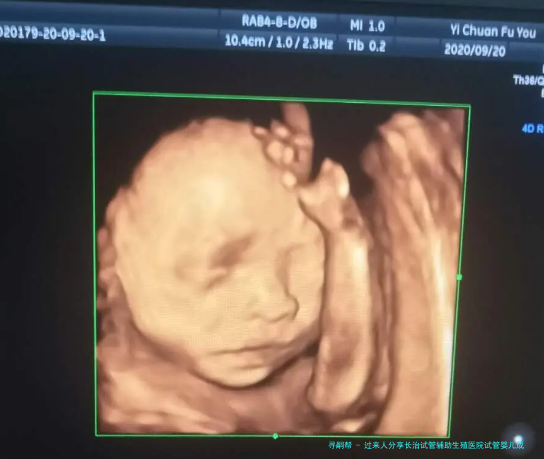

试管婴儿是一种当代的生殖技术,适用于没有办法自然受孕或存在生育困境的夫妇。长治试管辅助生殖医院作为一家专业的怀孕机构,提供了高质量的服务和高端技术,许多夫妻通过这里顺利实现了生育梦想。

试管婴儿的过程怀孕括助孕、精处置、胚胎培育和胚胎移植等步骤。在助孕阶段,医生会通过超声疏通下经阴道穿刺抽助孕。然后,从男方提供的精液中筛出质量相较好的精,并与卵进行怀孕怀孕。随后,培育得到的胚胎会在实践室中进行进一步培育,以保障其发育良好。比较后,经过医生明确较量争论和操作后,将合适的数目和质量的胚胎移植到女性一方本人身内。